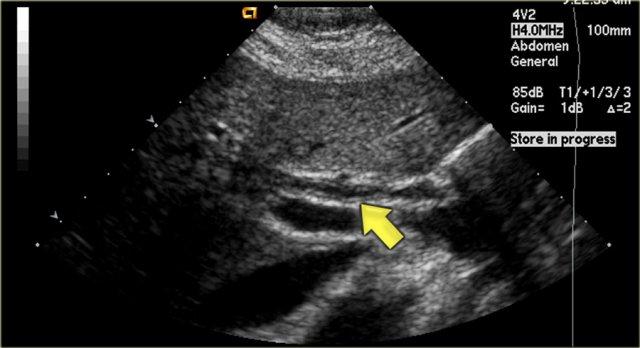

Hình ảnh Siêu âm

Một trong những dấu hiệu sớm nhất của PSC được phát hiện trên siêu âm là hình ảnh thành ống mật dày lên như thấy trong hình bên trái.

Bệnh nhân này đến khám siêu âm để loại trừ sỏi túi mật.

Lưu ý rằng các ống mật trong gan vẫn bình thường.

Chẩn đoán phân biệt bao gồm PSC, viêm đường mật liên quan đến AIDS và ung thư đường mật.

Ung thư đường mật ít có khả năng xảy ra hơn vì không có hình ảnh tắc nghẽn.

Tiếp tục xem hình ảnh CT.